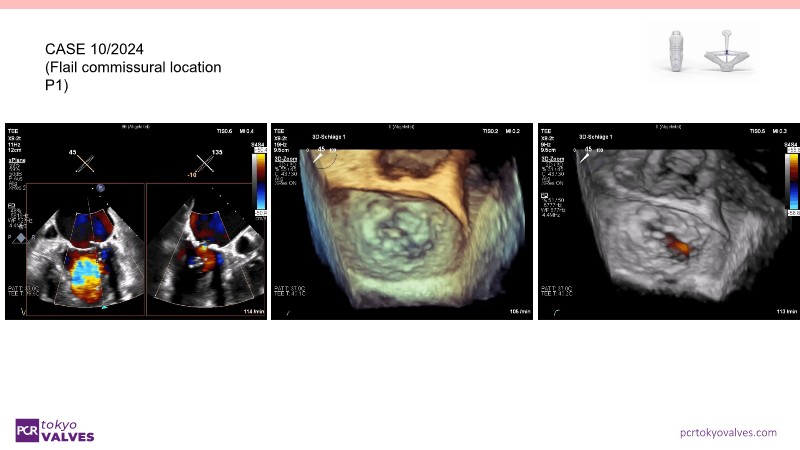

Through case reviews, explore the latest advancements in transcatheter edge-to-edge repair (TEER) for degenerative mitral regurgitation. Discover how a novel TEER device expands treatment possibilities, offering predictable and durable results.